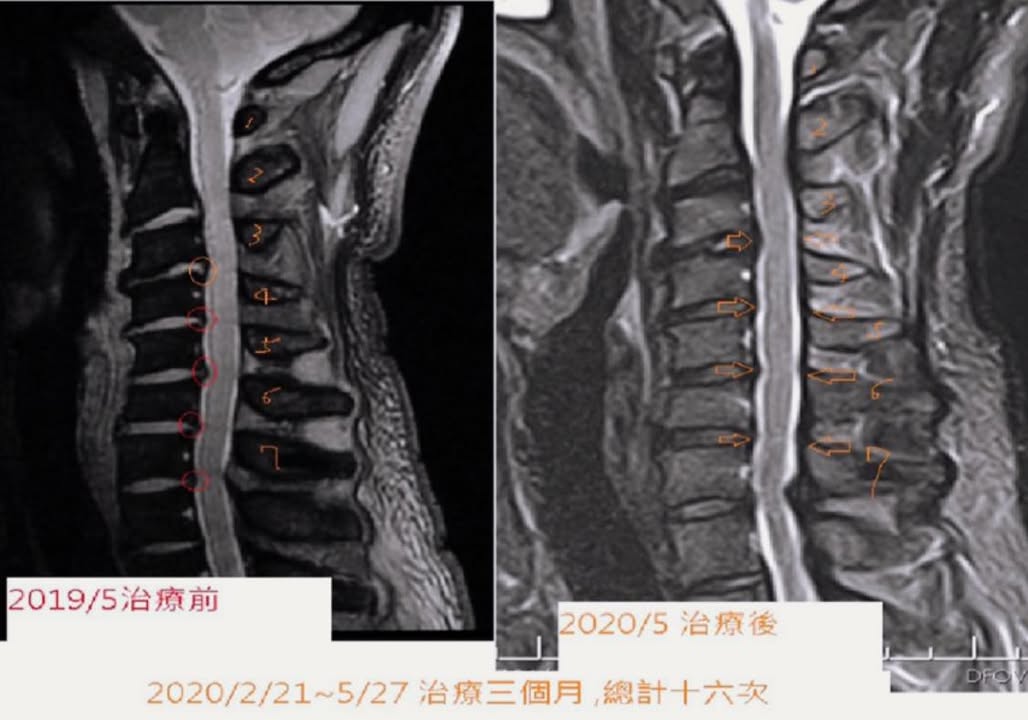

影像醫學前後對比:

之前有幾乎快五個卡壓點,進行十六次治療跟頸椎復位操的復健,椎管有三個點明顯打開,研判頸椎弧度從直線變成曲線,在同一張縱切面發現椎管容積打開,唯獨黃韌帶增生性肥厚還沒改善,患者臨床症狀完全消失又看到影像醫學有椎管打開跡象,很振奮人心,消失的頸椎曲線真的回來了!!

治療訪談:2/21~5/27,第三次治療就有改善,歷經漫長三個月的治療總共十六次,症狀完全消失,改善超過九成!肩痛完全不見,手麻只剩疲累偶爾出現幾秒,跟過去一麻就是超過好幾天有非常明顯的改善。